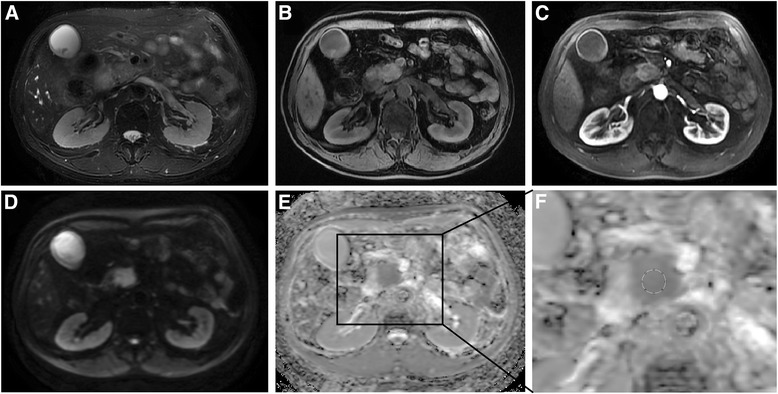

Based on the DWI images with b values of 0 and 600 s/mm2, ADC maps were calculated using a monoexponential model (ADC = (ln (SIb0/SIb600))/600) on a workstation (Function V9.4.05, AW 4.4, GE Healthcare). The ADC maps were reconstructed automatically with a 380 × 380 mm2 field of view (FOV) and a 256 × 256 matrix. The anonymous MR images of patients were sorted in a random order. The MRI data were evaluated and analyzed using ImageJ software (v1.47; http://rsb.info.nih.gov/ij). Six round ROIs (areas: 20, 46, 82, 115, 152, and 214 mm2; pixel numbers: 9, 21, 37, 52, 69, and 97) were drawn on the solid part of the tumor as identified on contrast enhanced T1WI (Fig. 1) while avoiding cystic lesion, dilated pancreatic ducts, and necrosis by referring to T2WI or T1WI images in both the six separate measurements. The mean ADC value and its standard deviation (SD) within each recorded ROI were obtained. All of the ADC values of the PDAC were independently measured by two observers (with 11 and 6 years of experience in abdominal radiology). To evaluate the intra-reader variability, the tumors ADCs were measured twice by reader 1 with an interval greater than three weeks. The first measurements of the tumor ADCs from reader 1 were further used to evaluate the inter-observer variability of the ADC values.

Fig. 1.

MRI images of histological proven pancreatic cancer in 64-year-old man. a: Axial T2WI; b: Axial precontrast T1WI; c: Axial contrast-enhanced arterial phase T1WI demonstrating the hypovascularity of the mass; d: DWI image (b = 600 s/mm2); e: ADC map; f: zoomed-in ADC map that indicates a ROI with a size of 214 mm2 (pixel number: 97) was used to measure the tumor ADC values

Typical MRI images and the ADC maps used for the ADC measurements are demonstrated in Fig. 1. As illustrated in Table 2, no significant difference was observed in the mean ADCs among the 6 different-sized ROIs for all the three measurements of two observers (all P > 0.05). Box plots providing graphic illustrations of the study data are presented in Fig. 2. The homogeneity index increased with increasing ROI size (Table 2).